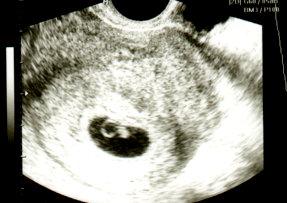

Hallo ihr Lieben wir waren heute nochmal beim FA. Es ist soweit alles gut. Das Herzchen hat gebubbert und sonst sieht unser Krümel noch aus wie ein Krümel Mein Arzt hat erst durch die Bauchdecke geschallt. Da hat man zwar auch alles gesehen aber es war nicht so scharf wie ein vaginaler Schall. Wir wollten ja noch ein Bildchen. Daher haben wir den auch noch gemacht. Ich bin jetzt soooo erleichtert Nach meiner Rechnung mit 32 Zyklustagen bin ich heute 7+0 und nach der Computerrechnung vom Doc bin ich schon 8+4. Im Grunde ist es ja auch egal solange es unserem Zwerg gut geht! Hab euch das Bildchen angehängt.

Bild zu Arztbericht - Forum für August - Mamis